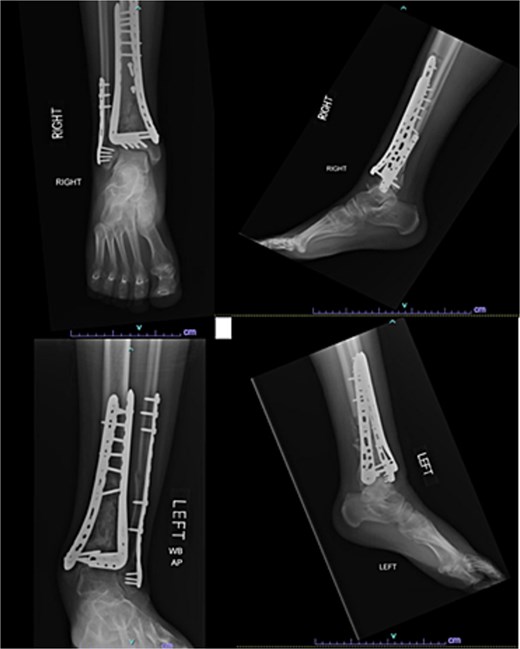

A 57-year-old male with a body mass index (BMI) of 48.7 kg/m2 and multiple comorbidities, including asthma, coronary artery disease, hypertension, hyperlipidemia, ischemic cardiomyopathy, obstructive sleep apnea, and hypothyroidism, following a motor vehicle collision when he lost control of his vehicle due to a coughing spell. His injuries included bilateral pilon fractures (Fig. 1), a T2 superior endplate fracture, and bilateral pulmonary contusions. He initially presented to a regional hospital and was transferred to our facility 10 days after the injury.

Anterior-to-posterior (AP) radiographs of patient 1 obtained 10 days after injury, upon transfer to our facility, demonstrating bilateral pilon fractures.

Surgical treatment occurred 2 days later. The left leg was treated via an anterior approach, with excision of several joint fragments and fixation using anterolateral and medial plates. The right leg underwent fixation with a distal fibular plate and placement of a circular ring fixator, which was removed 2 months later. The patient was initially wheelchair dependent because of non-weightbearing (NWB) on the left and toe-touch weightbearing (TTWB) on the right. After removal of the fixator, he transitioned to crutches with weightbearing as tolerated (WBAT) on the left and continued NWB on the right. He was compliant with these restrictions.